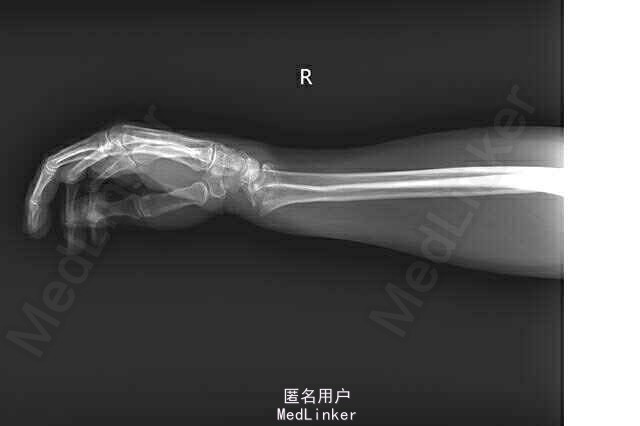

查体:第4、5掌指关节轻度肿胀,关节压痛(+),活动受限; 辅助检查:X线检查示:右手第4、5掌骨颈骨折,其中第5掌骨颈移位明显。

诊断:右第四、五掌骨颈骨折 行切开复位内固定术(LCP, Synthes, Titanium)